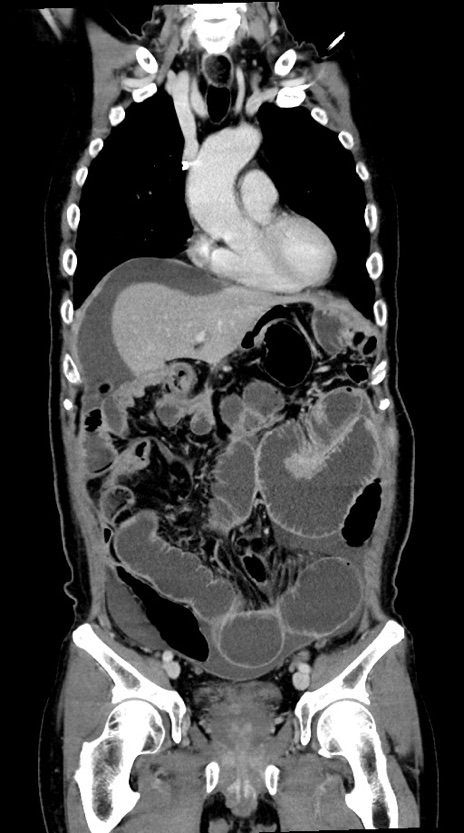

症例28(冠状断像)

【症例】60歳代男性

【主訴】嘔吐

【現病歴】胃癌にて胃全摘後。食思不振が悪化し、夜中に嘔吐することがある。

【既往歴】胃癌、胃全摘、脾摘、胆摘後

【データ】WBC 5900、CRP 10.56